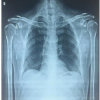

A 69-year-old female with a weight of 140 kg and BMI of 62.2 presented to us after twist and fall bathroom associated with left hip pain and inability to bear weight without any neurological deficit. She was operated on 1 year back for total hip arthroplasty (THA) for fracture neck of femur in the same hip (Fig. 1a, b).

X-ray pelvis with both hips was done, showing left prosthetic hip dislocation (Fig. 2a, b). CT scan was done to confirm the posterior dislocation of the hip (Fig. 3a, b, c, d). The version acetabular side and femoral side were found to be 15.6° and 17.8°, respectively. The anteversion of the acetabular cup was found to be 56°. The hip reduction was done under GA (Fig. 2a, b). The patient presented again 1 month later with the same dislocation. The patient was planned for implant exit from the acetabular side and revision dual mobile cup prosthesis implantation. On further investigation, we found the presence of deep vein thrombosis (DVT) in the patient. Preoperative DVT prophylaxis was taken as per cardiology consultation, and inferior vena cava filter was used.